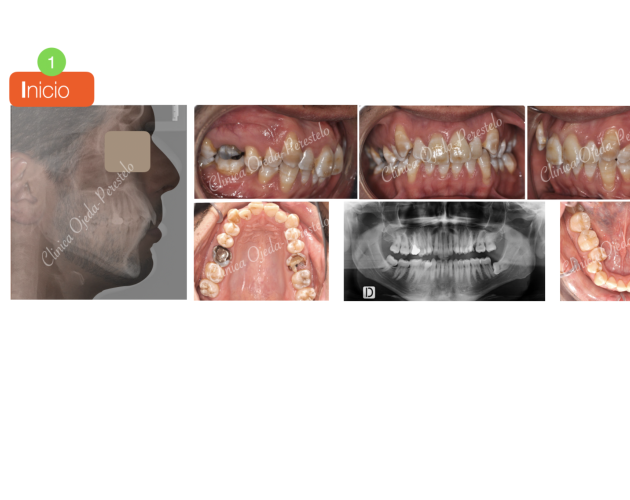

Casos de Éxito